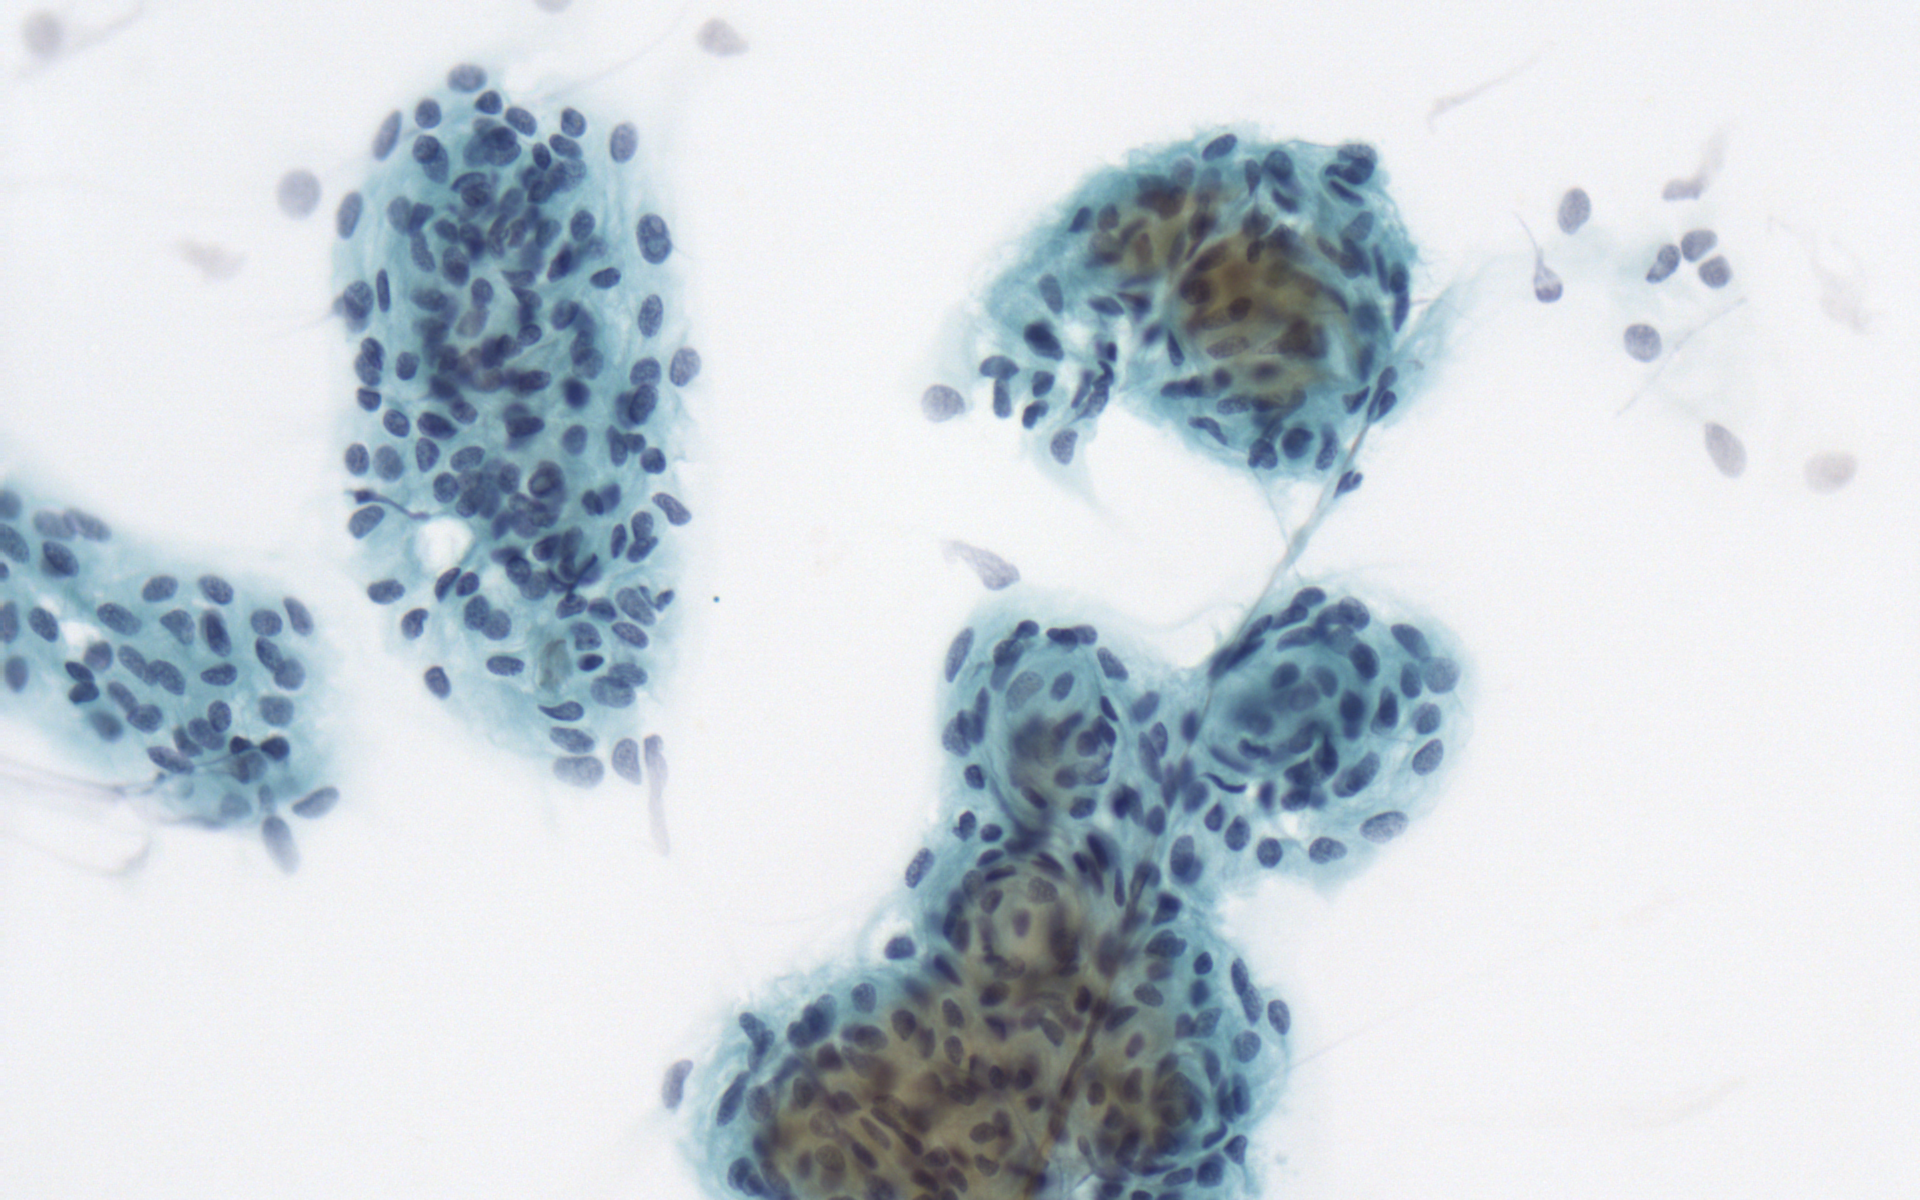

髄膜腫

【細胞像】

- 背景に砂粒小体を認めることもある

- 結合性を有する渦巻状構造をもつ集塊として出現する

- 腫瘍細胞は髄膜皮細胞に類似し、やや多辺形を示す。

- 核は中心性で核内偽封入体や核溝がみられることもあり、核縁は明瞭である。

- 核クロマチンは微細顆粒状で均等分布する。

甲状腺乳頭癌

【細胞像】

- 背景に、砂粒小体や組織球、リンパ球などを伴うこともある。

- 線維性間質結合織を伴った乳頭状ないし樹状集塊が出現する。

- 腫瘍細胞はライトグリーン好性で、扁平上皮細胞や好酸性細胞に類似する場合もある。

- 核は腫大し、核形不整(核溝)や核内細胞質封入体がみられる。

- 核クロマチンは微細顆粒状(すりガラス状)で、比較的均一に分布する。

- 小さめの核小体が観察されることもある。